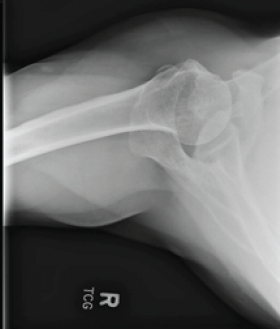

Complex Periprosthetic Humerus Fracture with Failed Osteosynthesis in an Elderly Osteoporotic Woman Managed with Vascularized Fibular Graft Augmented Fixation: A Case Report

Anand Kumaroth Somasundaram , S Jayachandran , Aiswarya Mohan , Anjali Appukuttan

………………………………p.63-68